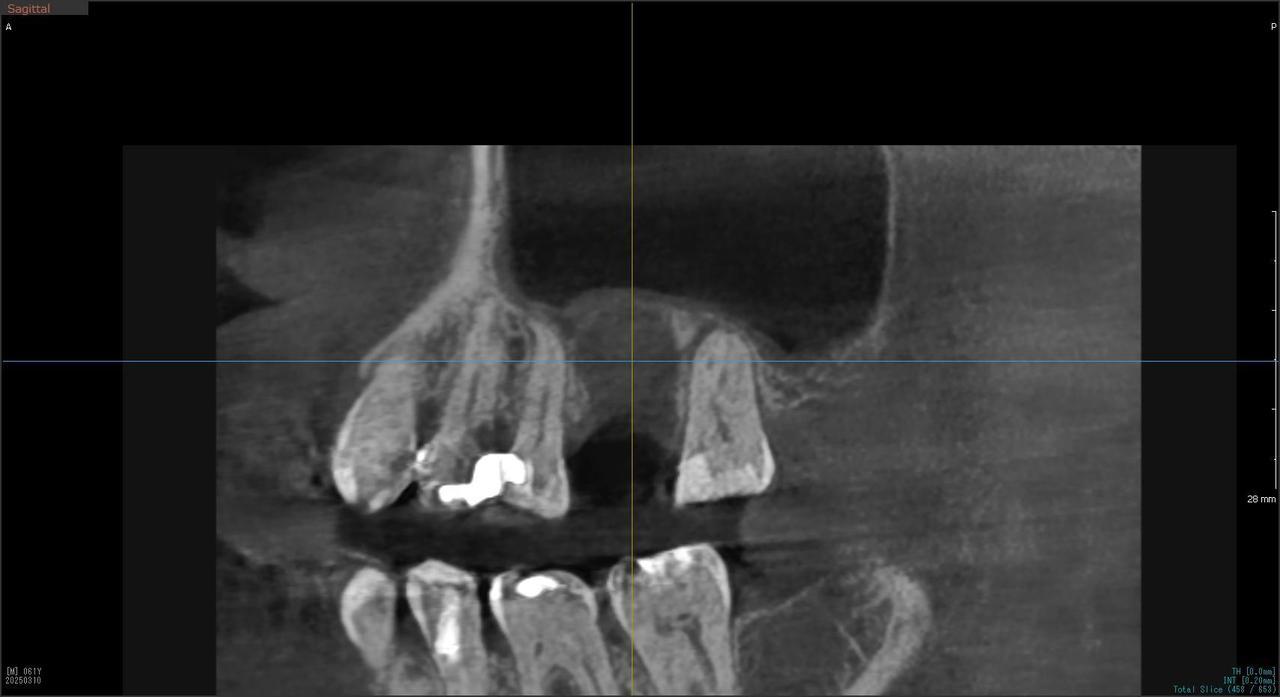

2.右上6番の上顎既存骨2mmのグラフトレスサイナスリフト(骨補填剤を使わない上顎洞挙上術)のケース

Before

枚方市のインプラントの症例

After

K・Y 様 女性 50代

症状としては、右上6番の歯が歯周病のため、自然に抜けてしまった。

治療法としては、歯周病により、右側6番の上顎骨が吸収して、2mm程度の骨しか残っていなかったため、サイナスリフトが必要であった。通常のサイナスリフトだと時間(時間的には1年から1年半程度かかると考えます。)と費用がかかり、患者様への時間的、肉体的、金銭的負担が大きくなることを考慮して、今回は、インプラントの種類としては、エクストラワイドショートインプラント、術式としては、デンサーバーを使用したグラフトレスサイナスリフトを選択しました。最終補綴物はジルコニアで仕上げています。

結果としては、高度に吸収した上顎骨に対するインプラント治療であったが、グラフトレスサイナスリフトを行うことで、短時間(2か月半程度)で治療を終えることができた。また、サイナスリフトによくある術後合併症である上顎洞炎を起こすことなく、患者様への肉体的な負担を抑えた治療を行うことができた。また、上顎右側6番にインプラント治療できたことにより、咬合が安定するとともに、歯周病にり患している上顎の他の歯に対する負担を少なくすることができた。

治療の期間・回数:約2か月半、6回

治療の価格:363,000円(税込)

治療費の内訳:インプラント基本料(フィックスチャー及び手術費用、投薬費用、レントゲン費用、インプラント上部費用(アバットメントおよびジルコニアクラウンの費用用)330000円(税込み)オプション費用グラフトレスサイナスリフト費用 33000円(税込み)

治療のリスクや副作用:手術後に、痛みや腫れ、出血、合併症などを引き起こす可能性があります。噛む感覚がご自身の歯と異なる場合があります。見た目がご自身の歯と異なる場合があります。手術後にメインテナンスを継続しないと、インプラントが抜け落ちる可能性があります。